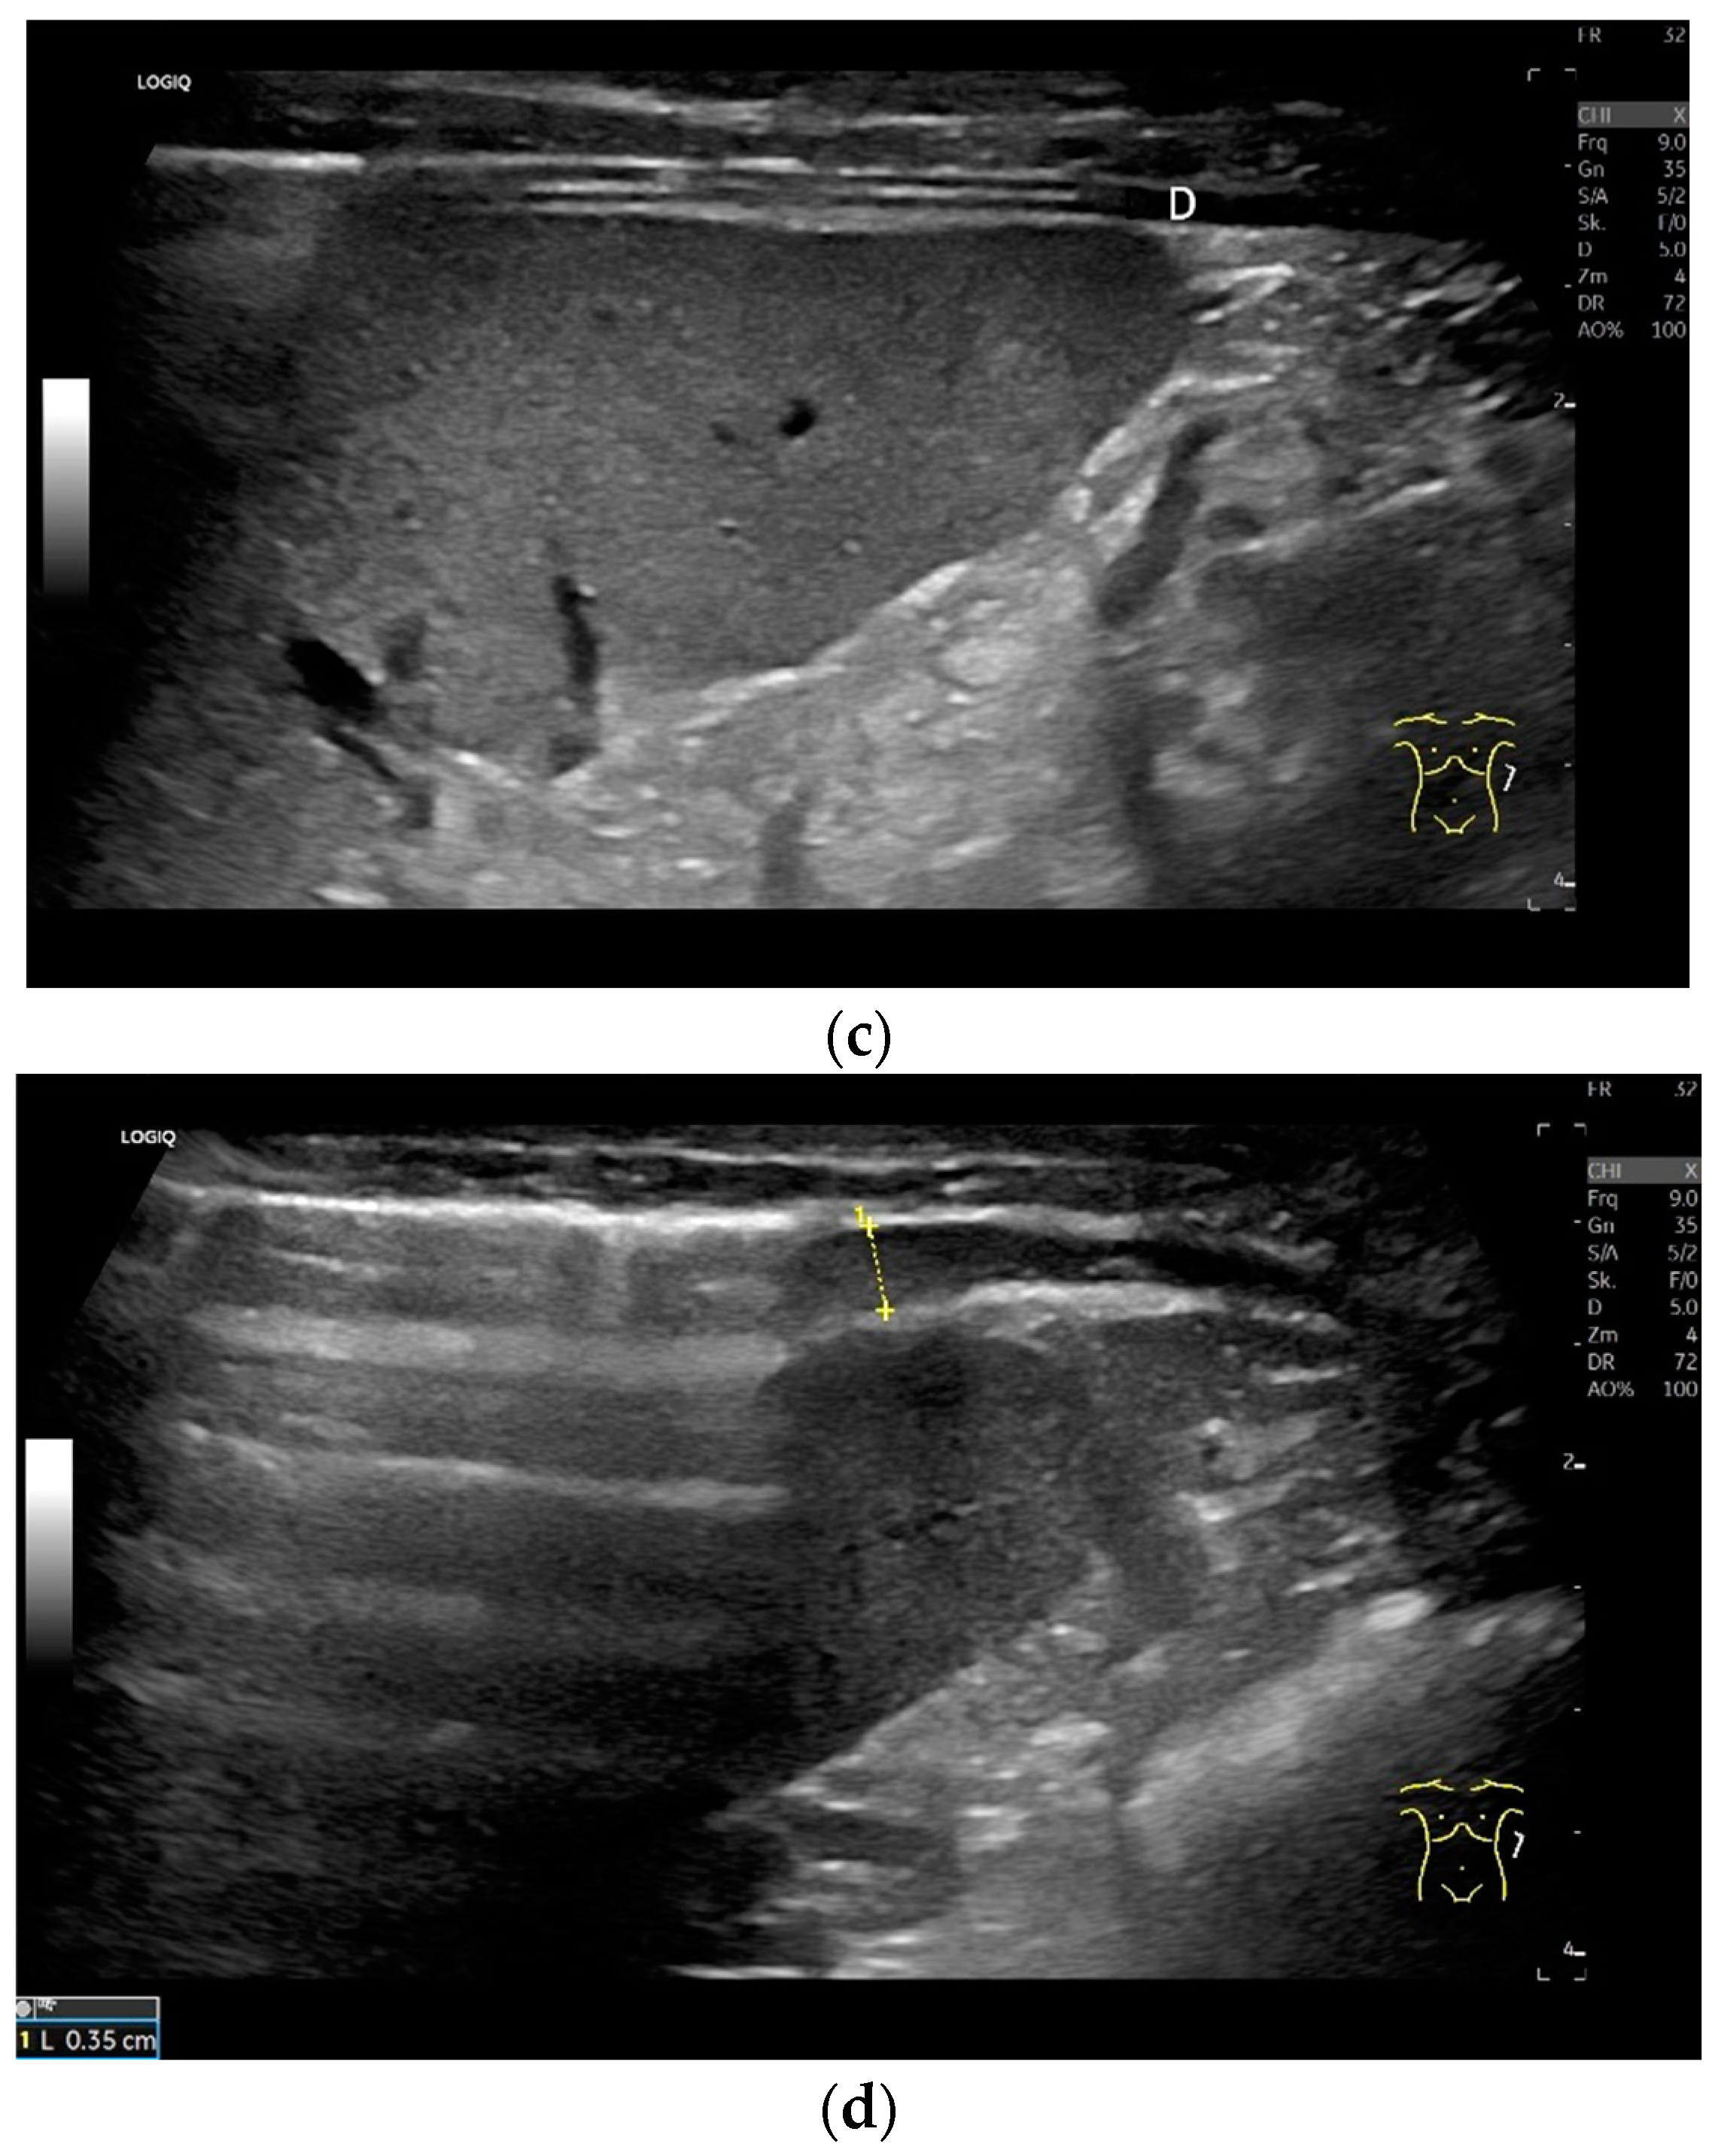

Regardless of the recommended positions for standardized measurements, the diaphragm can be viewed in other areas. This works quite well on the flank and subcostally in the midclavicular line (Figure 7).